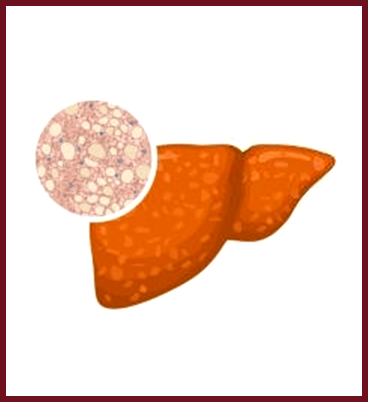

PBC a chronic disease characterized by progressive inflammation and destruction of small bile ducts within the liver. The bile ducts transport bile from the liver to the intestine for the absorption of fat and elimination of waste products.